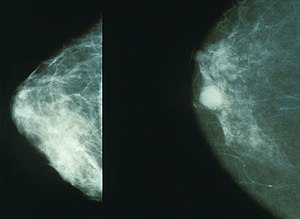

유방암은 유방에서 발생하는 모든 악성 종양의 그룹이라고 합니다. 유방암은 유방의 비정상적인 조직이 계속 자라거나 다른 장기로 퍼지는 위험한 질병이라고 합니다. 가장 두드러진 원인은 DNA 손상 및 유전자 돌연변이와 같은 유전적 조건입니다.

유방암에 걸리기 쉬운 특정 유전자를 가지고 있으면 비만과 마찬가지로 위험이 높아질 수 있으며, 과음, 흡연, 에스트로겐 노출, 가공식품이 많은 서구식 식단을 포함한 특정 식이 패턴도 유방암 위험을 높이는 것으로 나타났습니다. 따라서 유방암 위험을 줄이는 데 도움이 되는 식품을 파악하여 멍울을 완화하거나 예방하는 데 도움을 받아야 합니다.